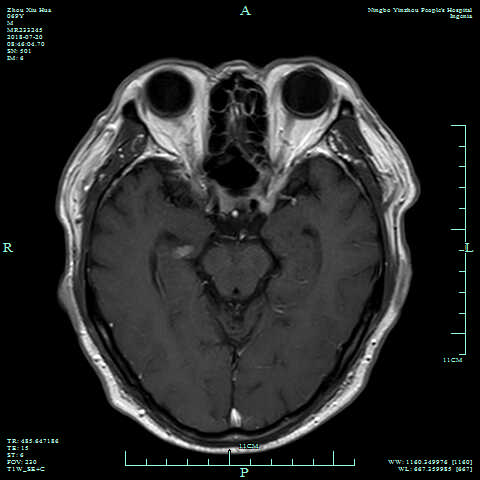

术后6月复查MRI,见肿瘤已全切,无残留。

图片2.png